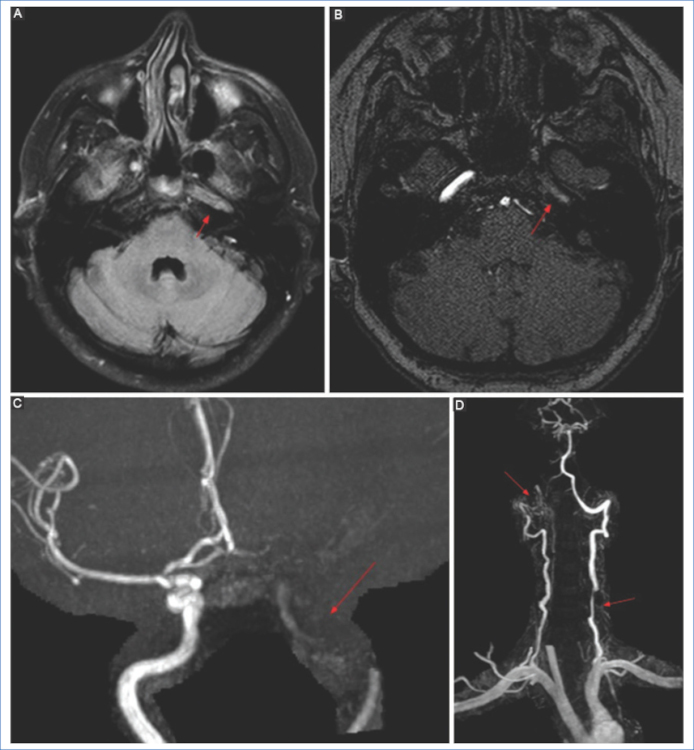

La adición de secuencias angiográficas con contraste que incluyan los troncos supraaórticos deben obtenerse incluyendo el arco aórtico, siendo de utilidad para evaluar la anatomía vascular, mostrar el sitio de oclusión, y además demostrar otras posibles fuentes embolígenas, como por ejemplo la presencia de aterosclerosis en la bifurcación carotídea o disecciones craneocervicales.

La disección arterial es una de las causas más frecuentes de stroke en pacientes adultos jóvenes.

El mecanismo es una ruptura de la íntima con extravasación del torrente sanguíneo hacia la pared vascular formando un hematoma intramural, aneurisma y estenosis. Esto produce que la arteria presente una morfología irregular con áreas de lobulaciones y estrechamiento.

Aunque un gran porcentaje de las disecciones cráneo-cervicales se consideran idiopáticas, las disecciones vértebro-cervicales pueden ser de origen hipertensivo o traumático13,20.

La disección de la ACI puede ser intracraneal o extracraneal. La disección extracraneal ocurre frecuentemente a 2-3 cm de la bifurcación21, mientras que en las arterias vertebrales se produce en el segmento V2 o V3.

Las secuencias angiográficas en la disección de la ACI pueden mostrar oclusión total con preservación del bulbo, o un segmento largo e irregular de estenosis filiforme por estrechez de la luz y engrosamiento parietal debido a hemorragia intramural (signo del collar de perlas) y/o pseudoaneurismas22 (Fig. 9). En la RM de las disecciones extracraneales, las secuencias ponderadas en T1 con saturación grasa son el mejor método para visualización del hematoma mural hiperintenso en las fases subagudas, debido a la metahemoglobina en el lumen falso13.